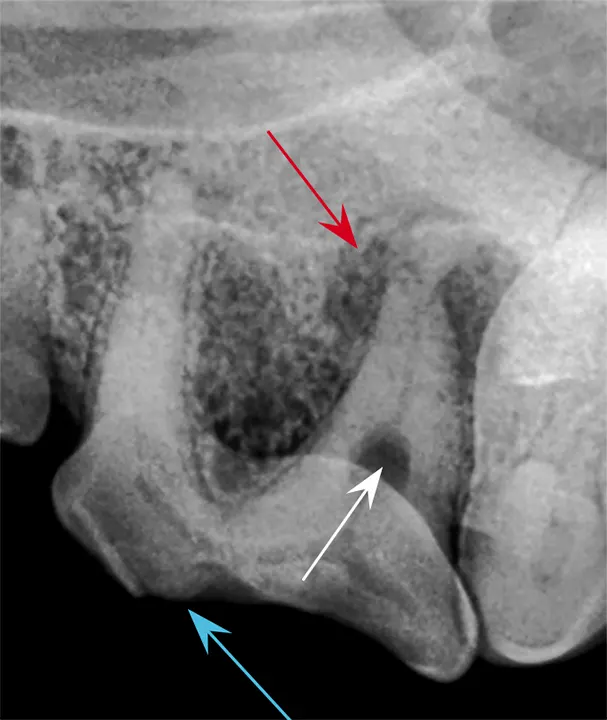

FIGURE 1: Periapical lucency

Periapical lucency develops secondary to bone loss around the tooth root caused by endodontic, neoplastic, or periodontal disease. In this dog, periapical lucency of the maxillary first and second molars (red arrows) developed secondary to periodontal disease. Periapical lucency secondary to endodontic disease (caused by exposure of the pulp from a slab fracture [blue arrow]) is also present surrounding the roots of the right maxillary fourth premolar (white arrow).

Observation of marked mobility of the molars would be expected on anesthetized examination. In this dog, the maxillary fourth premolar would likely not be mobile, as there is still bone surrounding the root apices. Extraction of the maxillary fourth premolar and first and second molars is indicated.